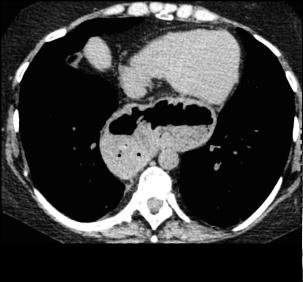

Hernie hiatale de type

I en coupe axiale TDM , fenetre mediastinale .

La poche hydro-aerique gastrique glisse alongee au

dessus hiatus oesophagien en arriere aureillete

gauche et ventricule gauche . |